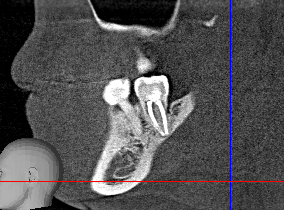

Group-4-5.png 321Кб, 860x355

>>1607542

>Киста внутри зуба, в канале?

нет, киста за пределами зуба на конце корня. Происходит из-за того что в канале инфекция, она выходит за пределы зуба в кость образуя очаг воспаления, который организм изолирует фиброзной тканью.

>Как то ощущалась вообще?

В большинстве случаев - хронический периодонтит никак себя не проявляет, может годами быть и пидарнуть при ослаблении иммунитета, может произойти дренаж содержимого через десну - т.н. свищ - что-то типа белого прыща на десне, может так же ощущаться при надавливании в области дислокации. Реактивный периодонтит - обычно вызывает, боль, отек, температуру - то что обычно называют флюсом.

>Как обнаружили кисту эту?

Сделать рентген или КТ.